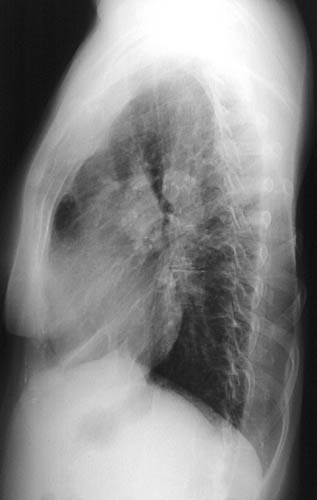

| The PA chest radiograph above and the lateral view below demonstrate cardiomegaly and prominent pulmonary arteries in a case of Eisenmenger complex. Eventually, failure of one ventricular chamber leads to failure of the other, and global enlargement, as in this case. Note that there is marked thoracic scoliosis. |